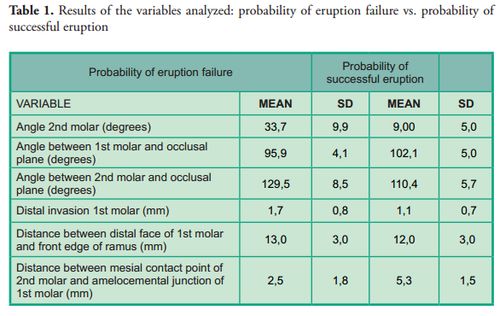

Patients with probability of eruption failure amounted to 1.43% of the sample, their mean age was 10 ± 1.7 years, and 73.3% of them were female. The variable used to determine the probability of success or failure of eruption was the angle of the second molar: an angle equal to or smaller than 24° showed probability of successful eruption, whereas an angle equal to or greater than 25° was considered with probability of eruption failure according to the average established by Evans in 1988 (average of 25° with a range from 15° to 65°). Tables 1, 2 and 3 show the results of the variables studied and their relation with the probability of teeth eruption or noneruption, unilateral or bilateral presence and distribution per quadrant.

This study of mixed dentition was conducted in the field of dental development with the aim to help prevent dento-maxillary anomalies in permanent dentition. We evaluated variables already studied by other authors to determine if this sample behaves in a similar way as previous samples or if it differs in some aspects. We found a 1.43% frequency of eruption failure of the second permanent molar. This percentage is similar to the results of Bondemark & Tsiopa in 2007 (1), who observed a prevalence of 0.8%, and of Cho et al. in 2008, which was of 1% (2). It differs from the findings of Sonis & Ackerman in 2011: 8.5% (8). Regarding the age of patients, we found a mean age of 10, as opposed to Sonis & Ackerman who reported a mean age of 11.2 years (8); 12.8 years for Evans (6) and 15 years for Magnusson & Kjellberg in 2009 (11). Regarding the angle of the second permanent molar, this study found a range from 25 to 80 degrees, which is similar to the findings of Cho et al. (13 to 75 degrees); Evans (15 to 65 degrees) and Sonis & Ackerman (19 to 33 degrees). The ranges described in the measurements of this angle are quite similar, which allows us to infer that patients with an angle included in the above ranges should be periodically checked. The invasion of the distal space of the first molar by the permanent second molar was of 1.7 mm in this study, which is greater than the invasion described by Sonis & Ackerman (0.57 mm). The angle of the second molar with regard to the line of the occlusal plane of this study was of 129.5 ± 8.5, which is smaller than the angle found by Shapira et al. in 2011 (134.66 ± 12.07).

The prevalence of risk of impaction of the lower second molar is low. The invasion of the distal face of the first molar in this study was greater than what was found in other studies. Risk of unilateral impaction is more frequent. Greater frequency of risk of impaction was found on the left side. No correlation was found between the size of the distal space of the first molar and the front edge of the ramus, and the risk of impaction of the second molar.